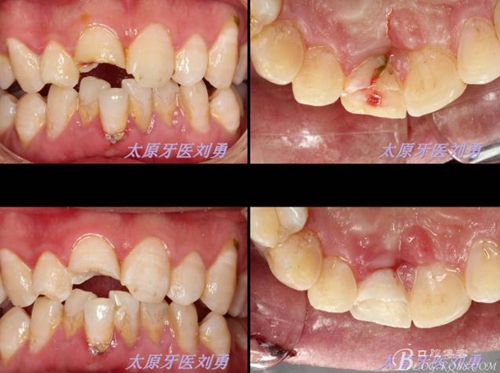

另外一例為本人高中同學,同樣不慎摔倒,導致A1折裂,露髓,且舌側(cè)有一碎片折裂至齦下3mm左右,先看術(shù)前圖片:

首先為了粘結(jié)斷端,選擇去除牙髓,行一次性根管治療后,首先處理舌側(cè)碎片,圖中可見舌側(cè)碎片裂至齦下,且牙齦有明顯撕裂,如果拔除折裂片,則難以修復,或者選擇牙冠延長或者選擇即刻種植,本人做了一種嘗試:粘結(jié)舌側(cè)碎片,首先對位碎片,發(fā)現(xiàn)對位后非常密合,如果采用全酸蝕粘結(jié)手段,則務必要掀開碎片,則有可能導致出血污染粘結(jié)面,導致粘結(jié)失敗。于是小心謹慎輕微掀開碎片,無滲血,用最小號毛刷蘸入自酸蝕粘結(jié)劑,然后直接復位碎片,并且壓緊,讓粘結(jié)劑能均勻擴散至斷面深處,光固化。術(shù)畢檢查,碎片粘結(jié)完好。如下圖: